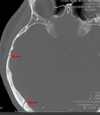

Which arteries do the arrows point to? [1]

Lenticulostiate arteries